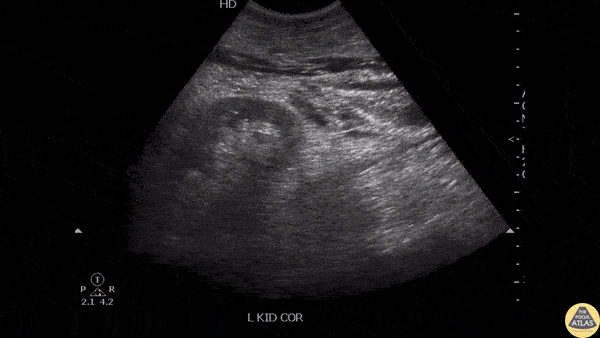

A patient with a history of ureteral stent placement presented with flank pain. POCUS revealed no hydronephrosis but shows signs of free retroperitoneal fluid likely due to erosion of the ureter by the stent. Image courtesy of Robert Jones DO, FACEP @RJonesSonoEM Director, Emergency Ultrasound; MetroHealth Medical Center; Professor, Case Western Reserve Medical School, Cleveland, OH View his original post here